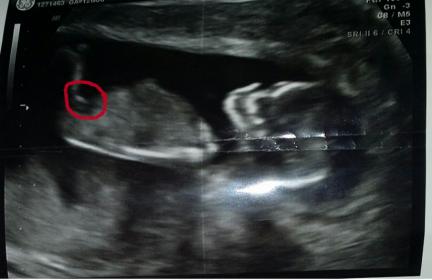

nuchal scan (NT procedure) is performed between 11 and 14 weeks of pregnancy, because accuracy is best in this period. scan obtained with the fetus and the fetal head neutral position (not hyperflexed or extended, both of which can affect the thickness of the nuchal translucent). Figure fetal enlarged to fill 75% of the screen, and the maximum thickness measured from the leading edge to the leading edge. It is important to distinguish the nuchal lucency of the underlying amniotic membrane.

normal thickness depends on (CRL) of the fetus. Among them are translucent fetal nuchal exceeds normal value, there is a relatively high risk of significant abnormalities.

How to determine a measurement of nuchal translucent normal or abnormal can be difficult. The use of a single millimeter cutoff (such as 2.5 or 3.0 mm) is inappropriate due to the measurement of nuchal translucent usually increases with gestational age (around 15% to 20% per week of gestation 10-13 weeks). At 12 weeks gestation, the "average" nuchal thickness of 2.18mm was observed; However, up to 13% of normal fetal chromosomes comes with nuchal translucent greater than 2.5mm. Thus for greater accuracy of predicting risk, nuchal scan results can be combined with maternal blood test results simultaneously. In pregnancies affected by Down syndrome there is a tendency for the rate (hCG) increases and (PAPP-A) will decrease.

Normal nuchal translucency measurement ( arrows ) at 12 weeks, 5 ... Nuchal Translucency Ultrasound - Prenatal Screening Ontario